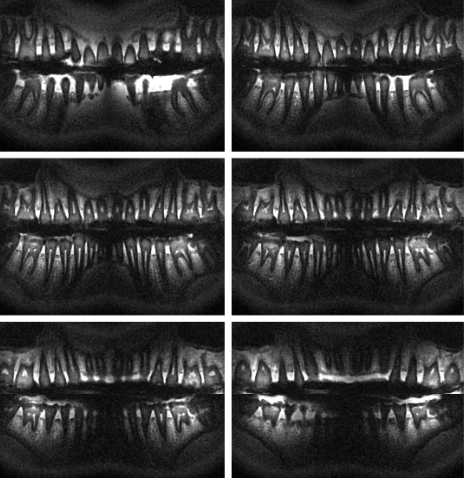

- Digital Radiography: Unlike traditional film-based X-rays, digital radiography uses electronic sensors to capture images, providing immediate results and reducing radiation exposure by up to 80%.

- Dr. Emily Nguyen, General Dentist: “Digital radiography has streamlined our workflow, allowing for quicker diagnoses and improved patient communication.”